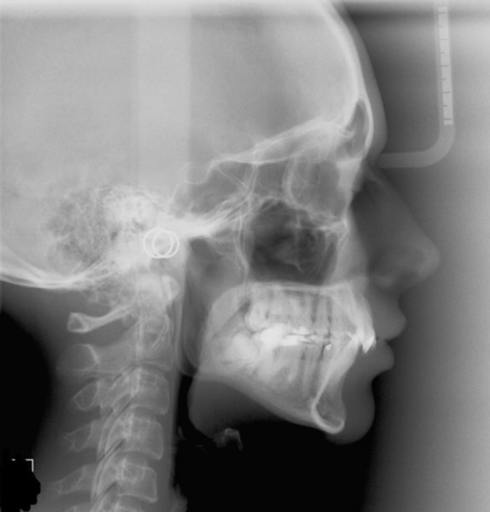

Do I require lefort 1 advancement?

I am 9 months post sarpe. My orthodontist said I should ask my surgeon if I should do lefort 1. My surgeon says I wouldn’t need lefort 1 advancement unless my ortho tilts my bottom front teeth out. What should I do and what questions and procedures...